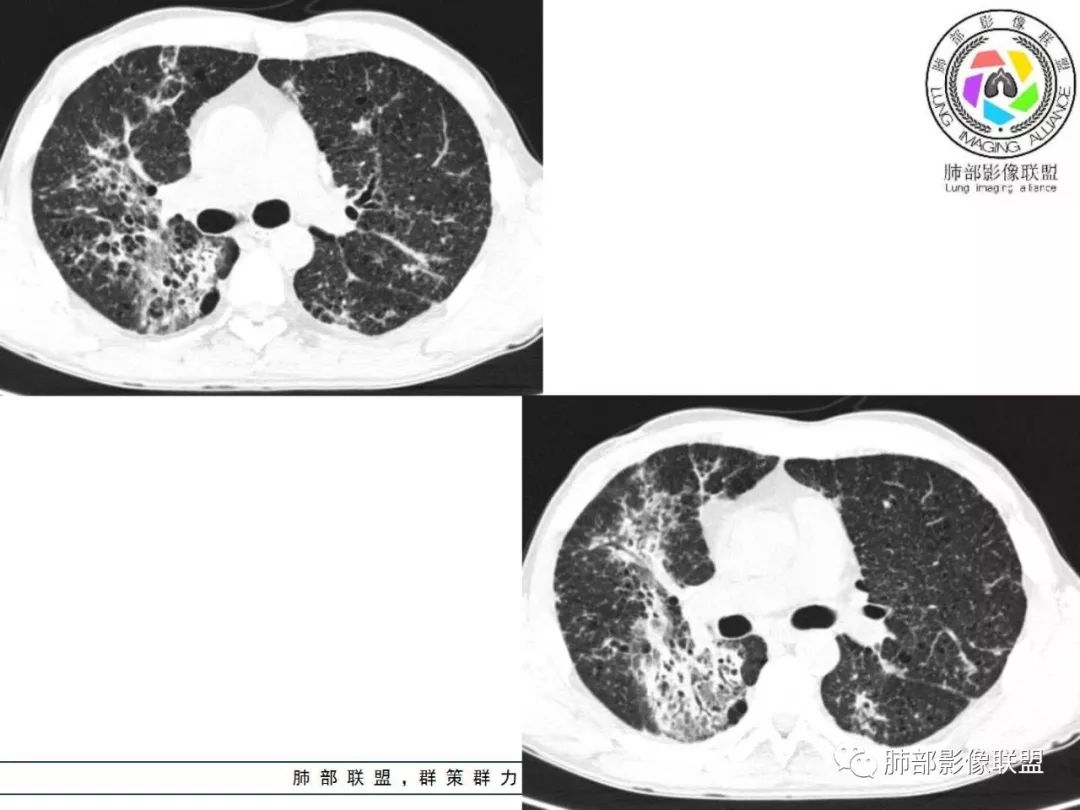

双肺间质性病变,中央间质增厚,胸膜下间质增厚,左侧胸膜肥厚,胸廓变小,肋间隙变窄。

胸部CT:两肺弥漫病灶,磨玻璃影,少许实变,部分累及胸膜,磨玻璃区可见囊?少许胸腔积液,两肺可见结节,支气管血管束增粗,小叶间隔增厚,支气管走形有扭曲扩张,可见纤维化。气肿、大泡。考虑:感染性病变,PCP?查下HIV,CD4,G等。鉴别结核、结缔组织病肺浸润。

胸部CT:两肺弥漫病灶,中央间质分布为主,部分位于胸膜及叶间裂旁,磨玻璃影,斑片影,部分实性结节,肺气囊,支气管血管束增粗,小叶间隔增厚,叶间裂不均匀增厚,支气管走形有扭曲扩张,可见纤维化、气肿、大泡。考虑:LIP加MALT。鉴别PLCH、PCP、结核、结缔组织病肺浸润。

双肺弥漫性病变,多发磨玻璃密度及小叶间隔增厚,大部分沿支气管血管束分布,伴支气管轻度扩张,以午后及晚上发热为主,考虑感染性病变,间质性结核可能大,另双肺多发肺气囊,LIP待排

病灶呈片状磨玻璃密度影,呈典型的烟花征。磨玻璃影密度偏高,有网结节样改变,与正常肺实质分界清楚,且常见相对高密度的勾画。

烟花征分为3肿类型:晕征、反晕征及均匀分布。

病变一般沿血管支气管束分布或小叶分布,一般上肺多于下肺(这与常见继发性肺结核分布相若)。

2. 肺气肿背景(小叶中心性肺气肿);双肺多发病灶整体沿血管支气管束及胸膜下分布,以上叶及下叶背段分布为主,有实变及GGO,边界清楚,有树芽,小叶间隔及中央间质增厚,叶间裂见到多发结节,部分支气管不规则牵拉扩张,提示病灶纤维化明显,结合临床病史,考虑病灶为间质性感染,肺门及纵隔内有钙化淋巴结,小叶间隔结节,考虑淋巴道增值性疾病可能,综合常规要怀疑间质性肺结核。